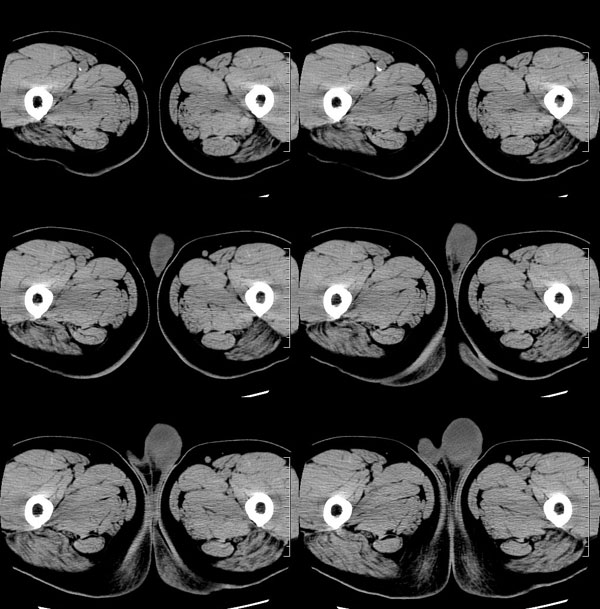

| 男性,69岁。自2个月前开始无意中发现左侧阴囊内一鸡蛋大小肿物,当时无伴疼痛等不适,未予重视。肿物逐渐增大,近段时间常伴左会阴部、腹股沟区牵扯不适,并于2周前在我院门诊行彩超检查提示“左侧附睾肿瘤可能,左侧睾丸鞘膜积液”。 专科检查:左侧阴囊肿大,其内可触及一鹅蛋大小肿物,表面光滑。肿物前部呈囊性感,后部质硬,按压无疼痛,无缩小,活动度良好。左侧睾丸未触及,透光试验(±)。                 王仕学发言:左侧睾丸见一密度不均肿块,边缘清楚,周围见水样密度影;考虑睾丸生殖细胞性肿瘤可能性大. 睾丸肿瘤占生殖系统肿瘤的3%-5%,占男性恶性肿瘤的0.5%-1.0%,其中生殖细胞性肿瘤占95%.睾丸肿瘤包括生殖细胞和非生殖细胞肿瘤两大类,前者占95%以上,后者不到5%.非生殖细胞肿瘤虽少见,但种类繁杂,主要有支持细胞、间质细胞和支持细胞-间质细胞瘤等功能性肿瘤,和间皮瘤、腺癌、横纹肌肉瘤、粘液性囊腺瘤、纤维上皮瘤、黑素神经外胚瘤、淋巴瘤等附属组织肿瘤。不同的病理类型的睾丸肿瘤发病率高峰不同,睾丸癌多发于35岁以前,精原细胞瘤发病高峰为30-35岁。精原细胞瘤约占睾丸肿瘤的60%,发病高峰在30-35岁。85%的患者睾丸有明显肿大,肿瘤局部侵犯力较低,肿瘤一般有明显界限。 手术:行“左侧附睾、睾丸、精索切除术”。 病理诊断:(左睾丸、附睾)肿物,为低分化腺癌。另送检(左精索远端)肿物,镜下亦为低分化腺癌。 免疫组化:ck(l)(++++)、cea(+++)、ca19-9(-)、psa(-)、plap(-)、p53(-)、vimentin(-)。 原贴地址:http://www.radinet.com.cn/forum_view.asp?forum_id=4&view_id=30707 |